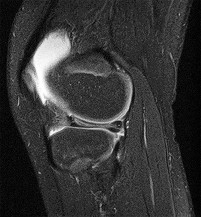

Question 4:

A 22-year-old female soccer player undergoes primary anterior cruciate ligament (ACL) reconstruction using a bone-patellar tendon-bone autograft. Postoperatively, she experiences loss of terminal extension and anterior knee pain. An MRI indicates graft impingement against the intercondylar roof. Which of the following technical errors during tunnel preparation is the most common cause of this specific impingement pattern?

Correct Answer: Tibial tunnel placed too anteriorly

Explanation:

Placing the tibial tunnel too anteriorly is the most common cause of intercondylar roof impingement. The tibial tunnel should be placed posterior to the intersection of Blumensaat's line and the tibial plateau when the knee is in full extension. If placed anterior to this line, the graft will impinge on the notch roof during terminal extension, leading to a loss of extension and potential graft failure.